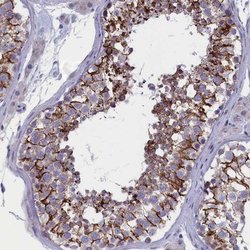

Supportive validation

- Submitted by

- antibodies-online (provider)

- Main image

- Experimental details

- IHC